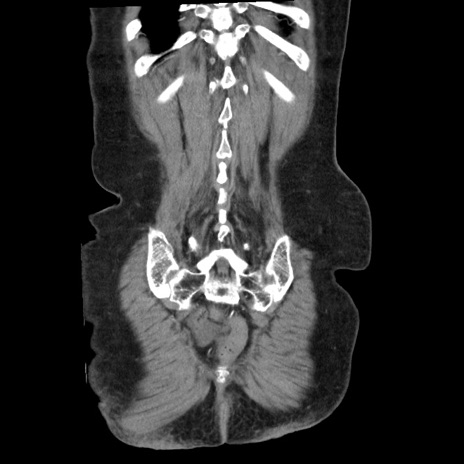

矢状断像

【症例】80歳代女性

【主訴】腹痛

【現病歴】8時間前から腹痛あり来院。

【既往歴】糖尿病、脂質異常症、子宮体癌にて子宮全摘術

【身体所見】意識清明・会話良好だが腹痛で苦悶様、全腹部にわたって反跳痛と圧痛あり

【データ】WBC 13600、CRP 0.14、LDH 224、CK 90